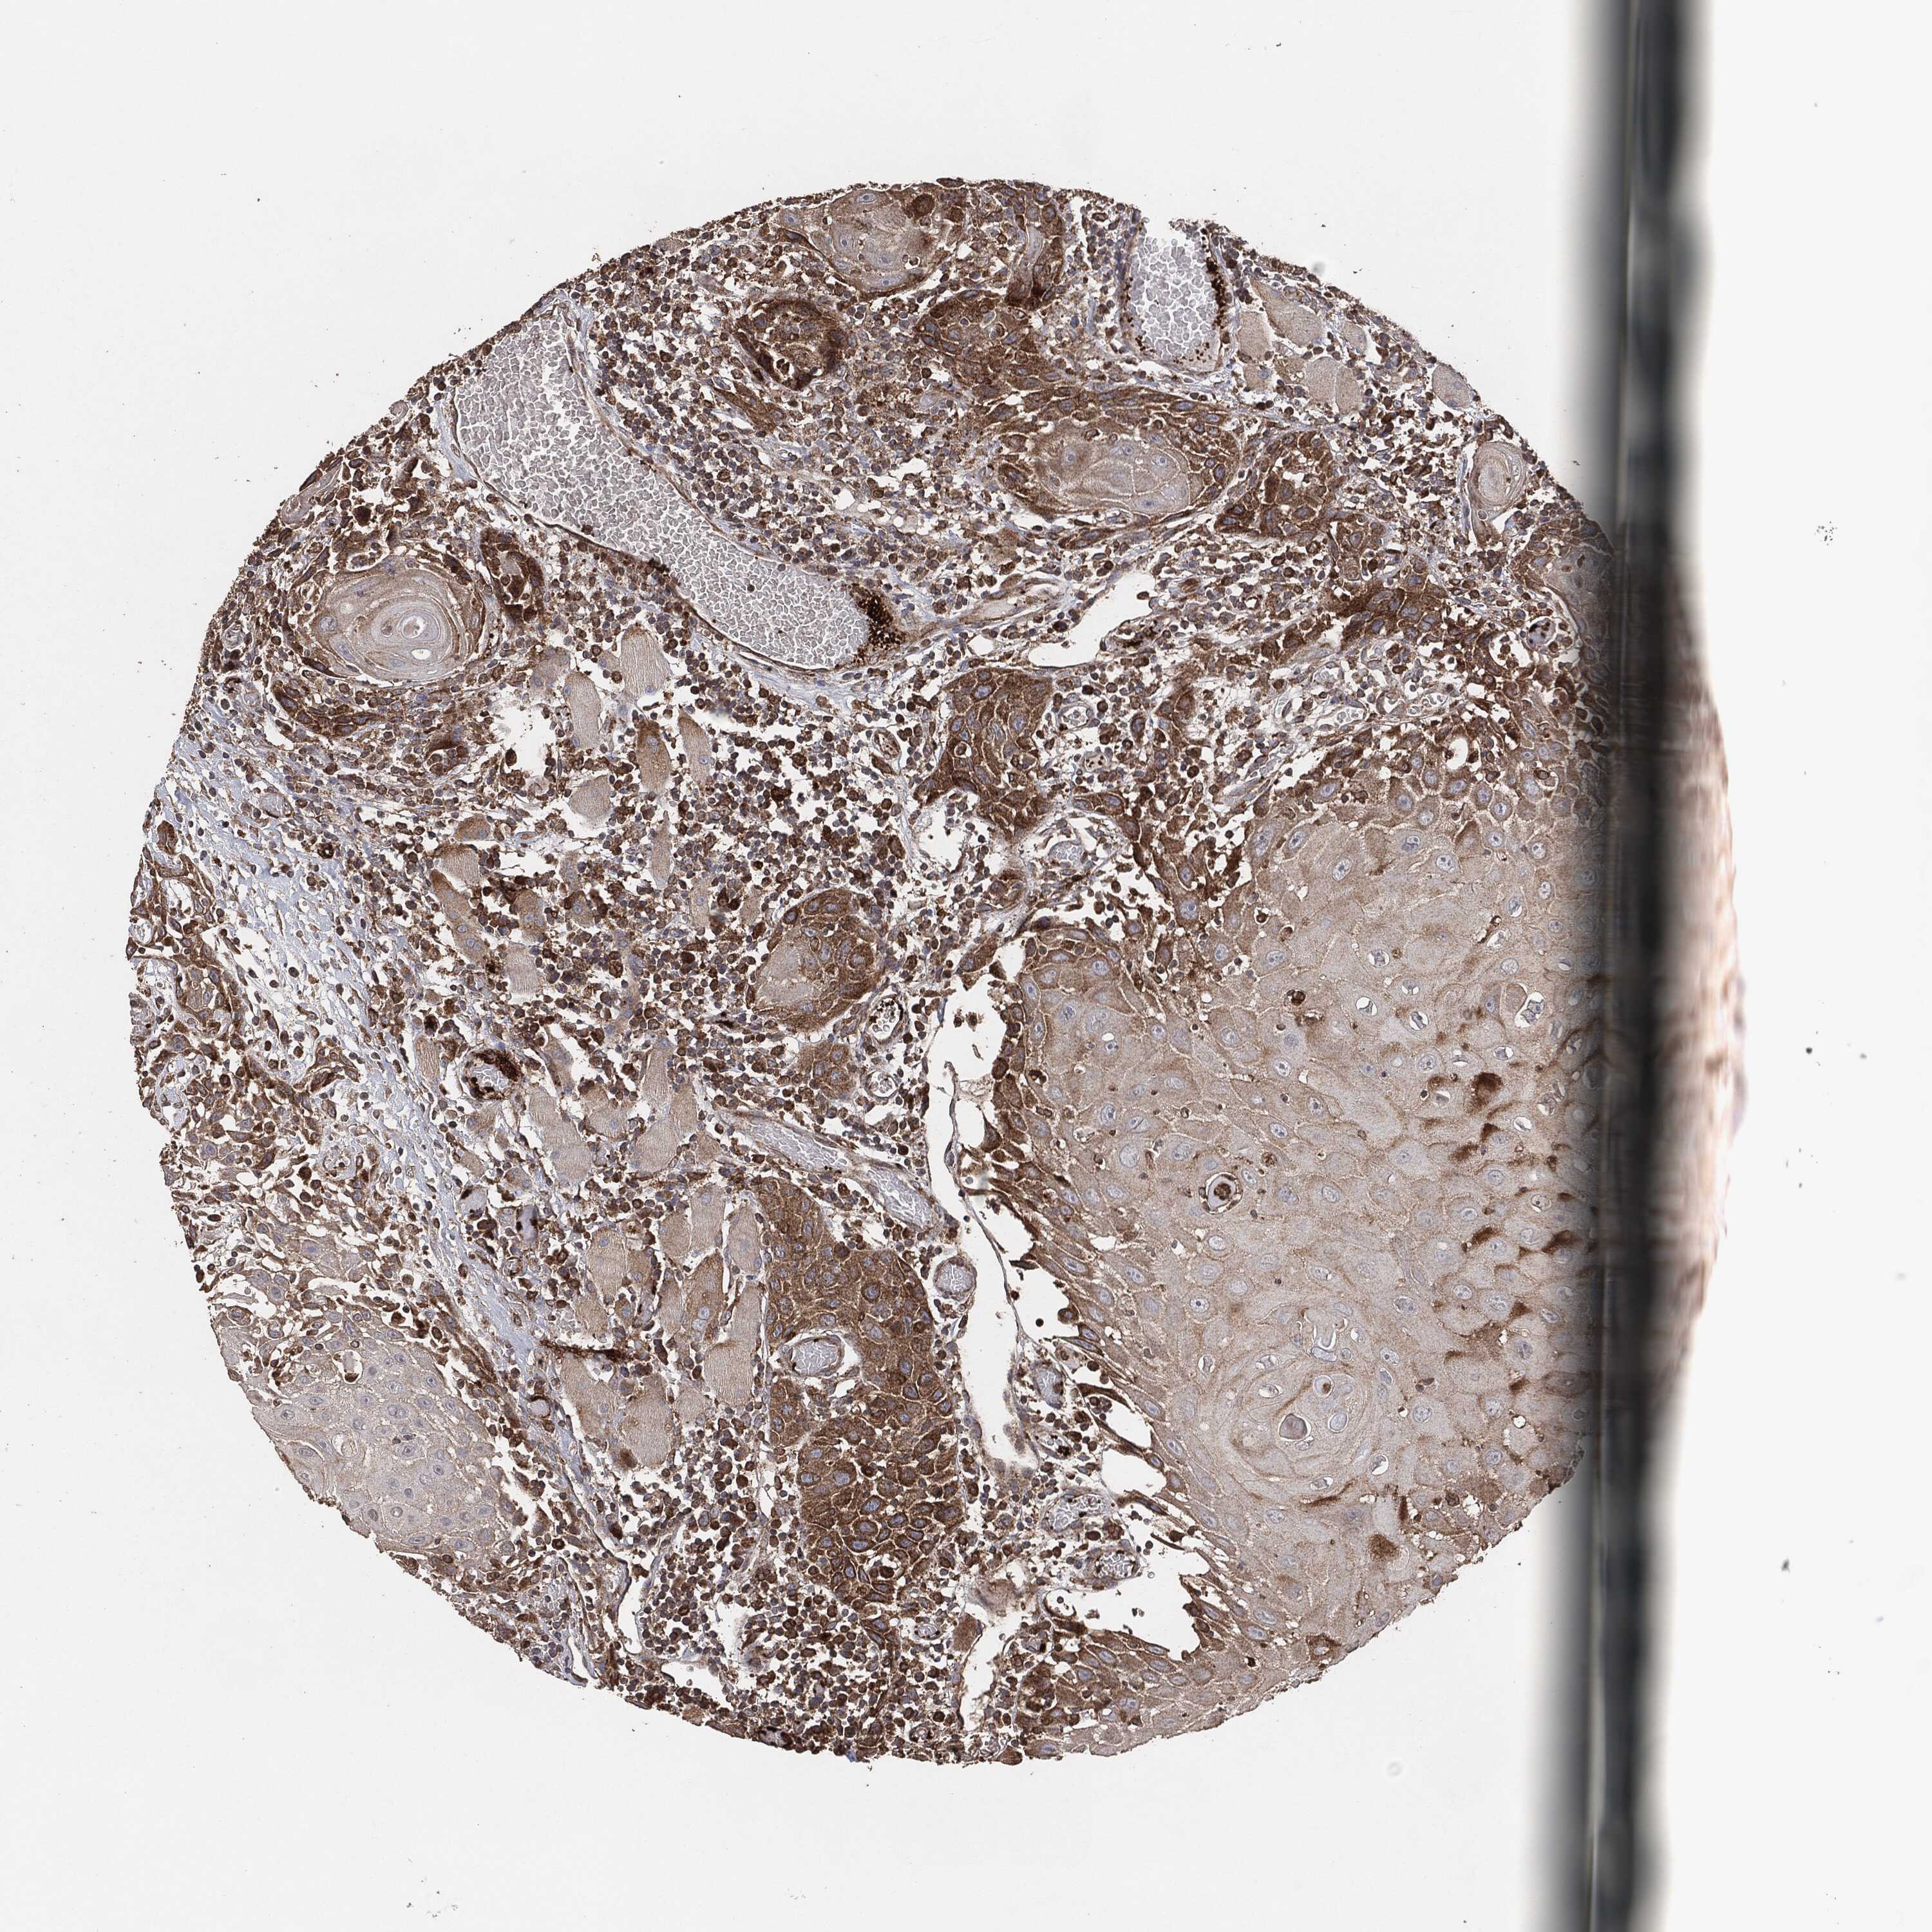

HEAD AND NECK CANCER - Protein expressioni

A mouse-over function shows sample information and annotation data. Click on an image to view it in a full screen mode. Samples can be filtered based on level of antibody staining by selecting one or several of the following categories: high, medium, low and not detected. The assay and annotation is described here.

Antibody stainingi

Antibody staining in the annotated cell types in the current human tissue is reported as not detected, low, medium, or high, based on conventional immunohistochemistry profiling in selected tissues. This score is based on the combination of the staining intensity and fraction of stained cells.

Each image is clickable and will lead to virtual microscopy that enables deeper exploration of all samples and also displays staining intensity scores, fraction scores and subcellular localization as well as patient and tissue information for each sample.